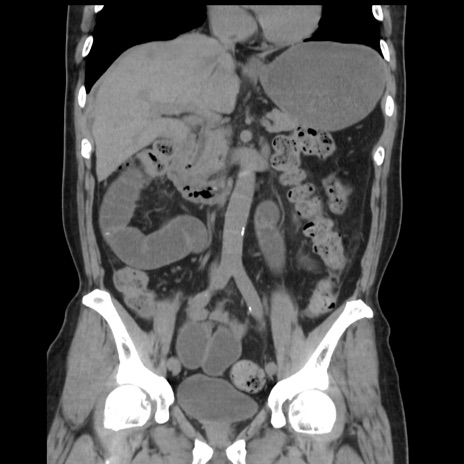

症例16(冠状断像)

【症例】 70歳代男性

【主訴】 腹痛、嘔吐

【現病歴】 約1ヶ月前より間欠的に腹痛と嘔吐あり、当院消化器内科を受診したところCTで多発する肝臓のLDAを指摘され、精査中であった。以降は消化器症状は安定していたが、2日前より嘔気と腹痛があり、同日より排便・排ガスが消失した。改善認めず、 本日、救急外来を受診した。

【既往歴】 大腸ポリープ切除後。

【身体所見】意識清明・会話良好、BT 36.3℃、BP 127/80mmHg、 P 80bpm、腹部:膨満あり、平坦・軟、上腹部正中および下腹部正中に圧痛あり、反跳痛なし、筋性防御なし。

【データ】WBC 7200、CRP 0.77